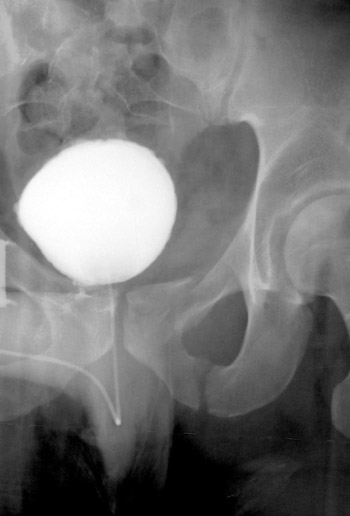

• Articular or para-articular fracture of the sacroiliac joint and ipsilateral ischiopubic rami.

• Due to the location of the fractures involved, a Malgaigne fracture renders the pelvis unstable.

• A Malgaigne fracture can often be recognized clinically as shortening of the ipsilateral lower extremity. Radiographic diagnosis can be made from an AP view of the pelvis.

Can you find all the fractures? Click on the image for the answer.